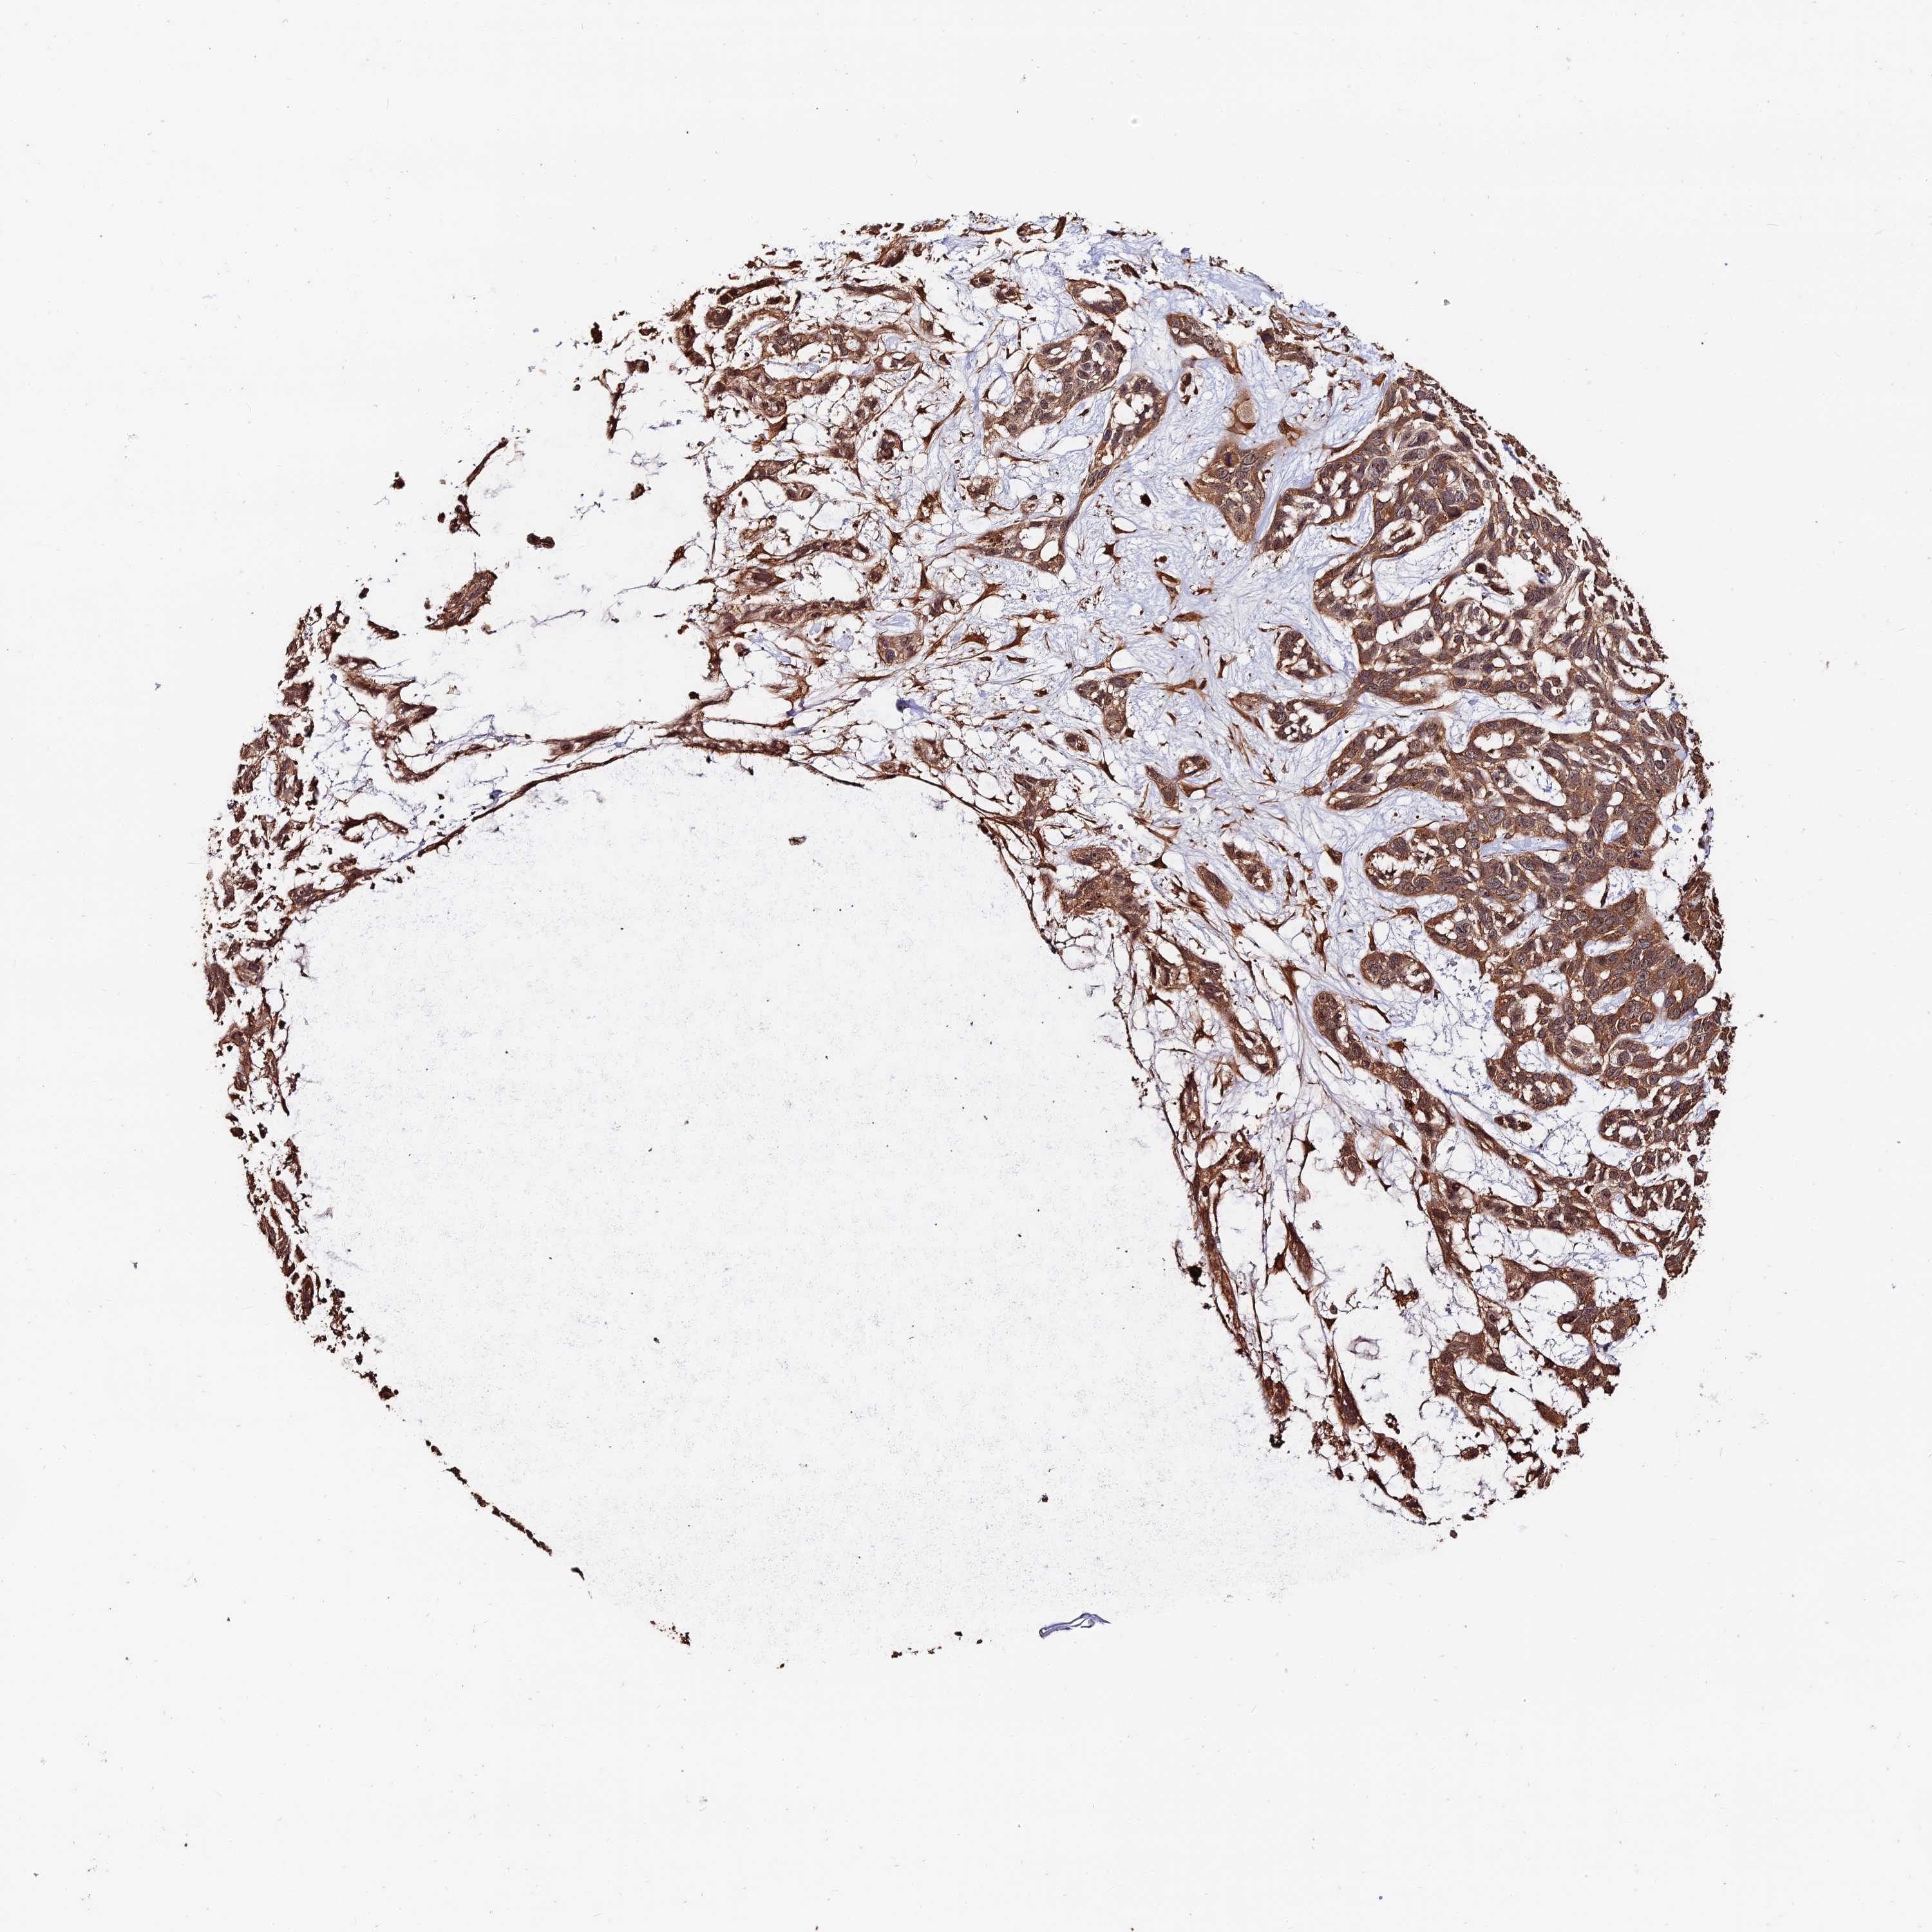

Basal cell and squamous cell cancer

SKIN CANCER - Protein expressioni

A mouse-over function shows sample information and annotation data. Click on an image to view it in a full screen mode. Samples can be filtered based on level of antibody staining by selecting one or several of the following categories: high, medium, low and not detected. The assay and annotation is described here.

Antibody stainingi

Antibody staining in the annotated cell types in the current human tissue is reported as not detected, low, medium, or high, based on conventional immunohistochemistry profiling in selected tissues. This score is based on the combination of the staining intensity and fraction of stained cells.

Each image is clickable and will lead to virtual microscopy that enables deeper exploration of all samples and also displays staining intensity scores, fraction scores and subcellular localization as well as patient and tissue information for each sample.

Antibody CAB002611

Squamous cell carcinoma, NOS